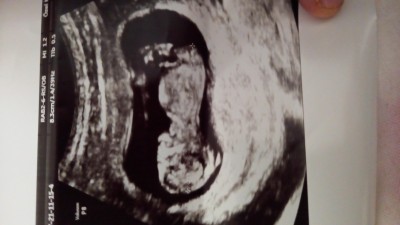

12 haftalik ultrason görüntüsü merak ediyorum cinsiyeti nedir hanımlar?

Gebelik haftası 12

Yüzde 60kiz :) sağlıklı olsun inşallah

Bende kıza benzettim